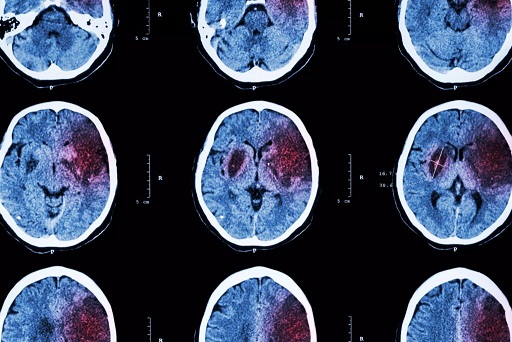

O diagnóstico do AVC é realizado por meio de exames de imagem, que ajudam a identificar a área afetada do cérebro e o tipo de derrame – isquêmico ou hemorrágico. A tomografia computadorizada de crânio é o exame mais utilizado, pois detecta rapidamente sinais de isquemia.